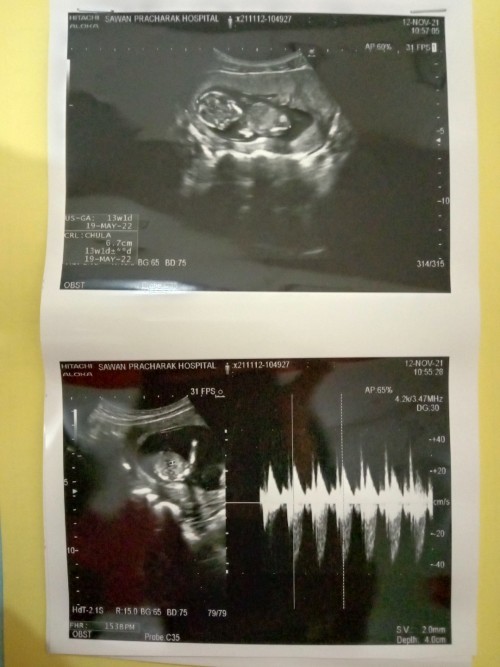

วันแรกที่มั่นใจว่าเราท้อง 3 เดือนแล้วคะ